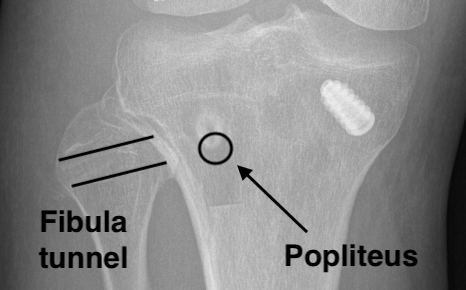

Tibia / Fibular tunnels

Fibular tunnel for LCL

- insertion of LCL is 8 mm from anterior fibular and 25 mm distal to fibula styloid

- tunnel will pass anterolateral in proximal fibular to posteromedial

- ensure that there is sufficient superior bone in fibular head

- if blow out fibular head will not be able to secure LCL

- place posterior retractor

- drill 7 tunnel protecting the CPN

Fibular tunnel 1Fibula tunnel 2

Popliteus tibial tunnel

- anterior entry point is distal and medial to gerdy's tubercle, below tibial plateau

- drill to 9 mm

Popliteus tunnel 1Popliteus tunnel 2